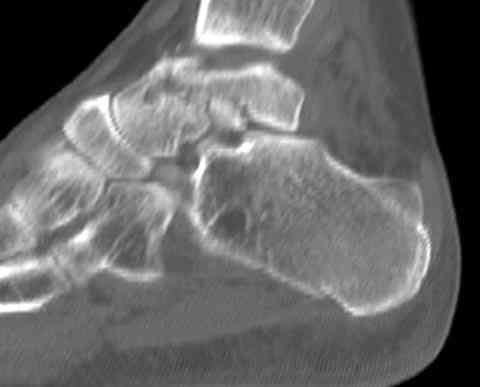

И второй случай из недавней ташкентской практики, (извините за

качество ренгенограммы и только в одной проекции) случай падения с

высоты (кстати моего друга - известного киноактера) - открытый

смещенный перелом тарана, с переломом переднего края дистального

эпиметафиза большеберцовой кости.

При поступлении в приемной сделана первичная обработка с ушиванием

открытой латеральной раны и вытяжением за пятку.

Из-за отсутствия времени пришлось оперировать на второе утро, из

материала, что имеем на месте, фиксирован двумя шурупами, а третий-это

контур сломанного жойстика в 4 мм. На дистальный медиальный конец

тибиа antiglide 3.5 мм пластина. Через пару дней выписан и несмотря на

предупреждение, самостоятельно начал нагрузку в 4 недели, время не

ждет, снимается в боевике в Росийской Федерации.

Имя     : talar fx.CT coronal 3.jpg

Тип     : image/jpeg

Размер  : 22746 байтов

Описание: отсутствует

Url     : http://weborto.net:8080/pipermail/ortho/attachments/20070615/61a2112e/attachment-0013.jpg